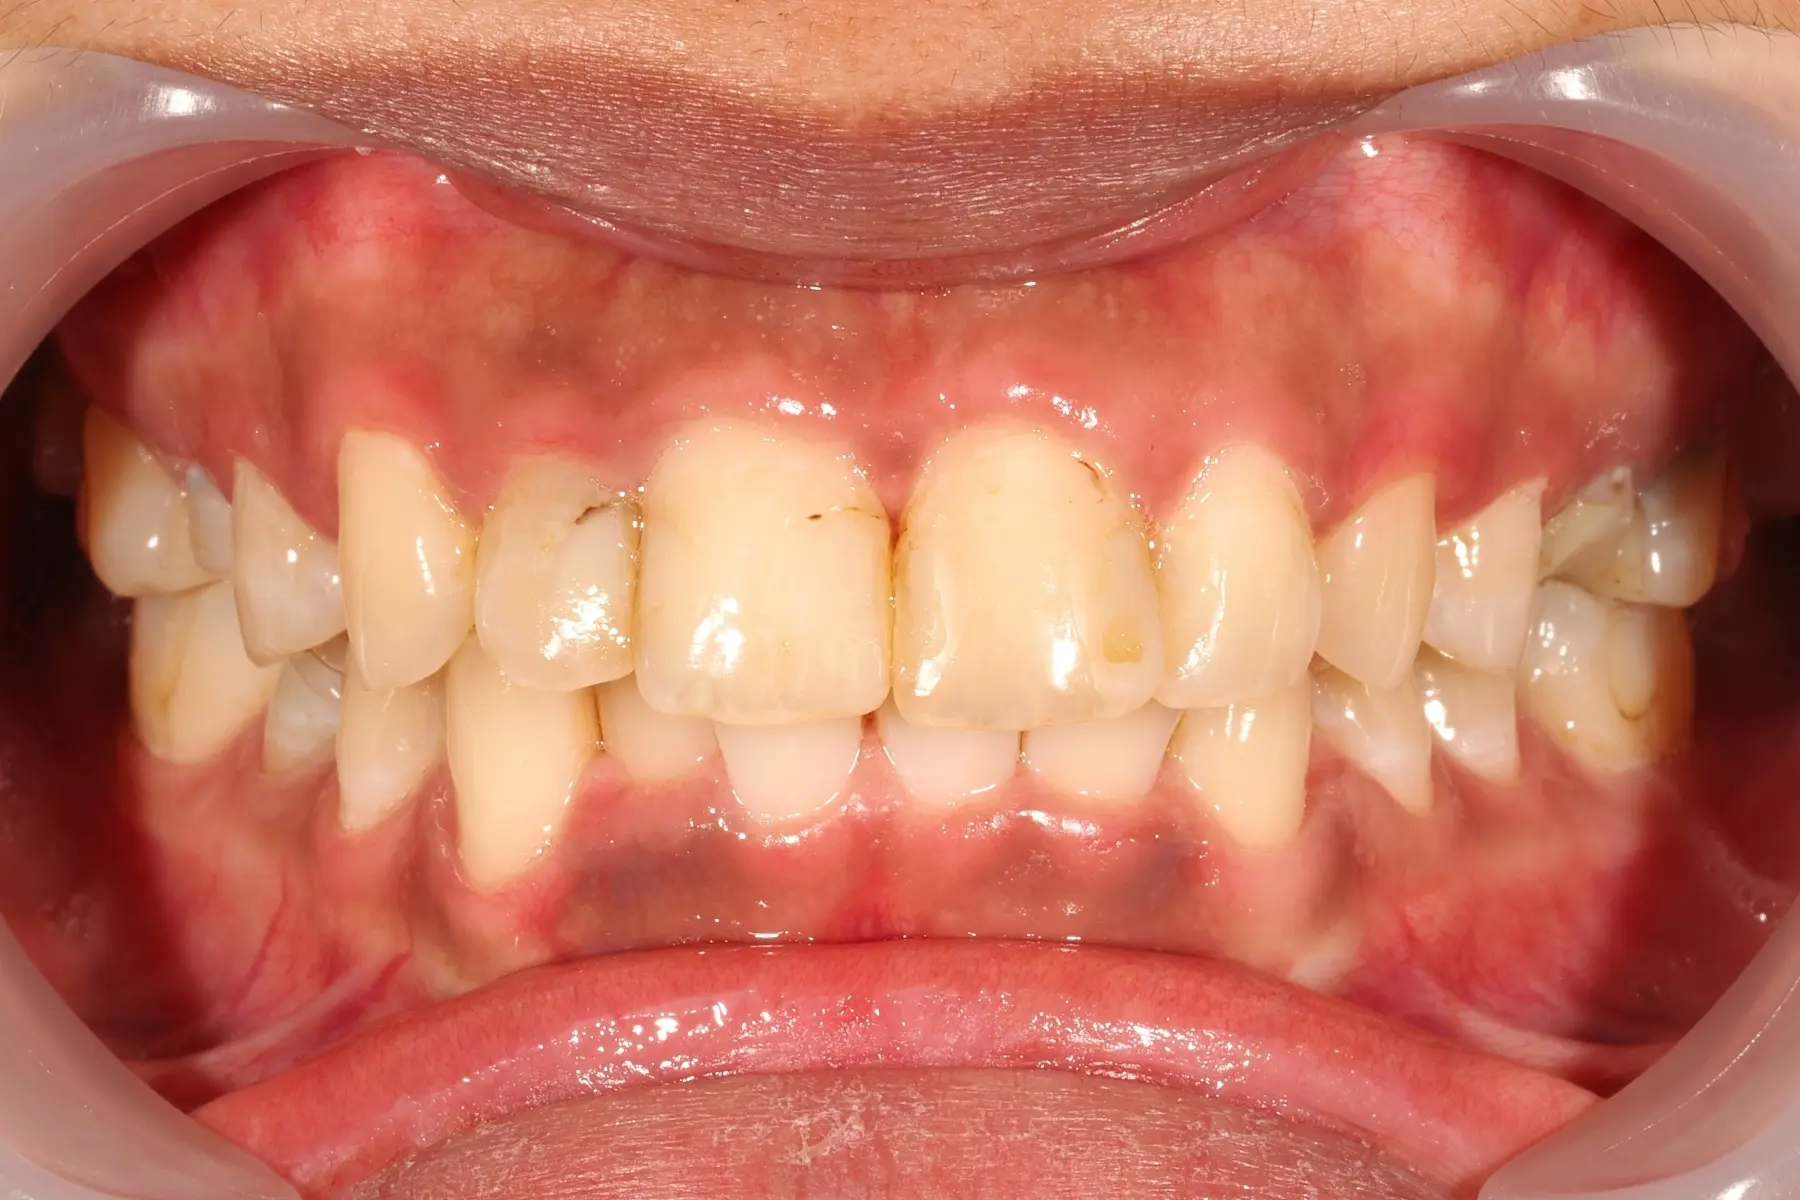

• 術前 44

術後 42

仿生美學樹脂

主治醫師

• 陳暐文

治療時間

單次療程

主訴

門牙有縫、牙齒形狀偏方,笑起來不夠自然